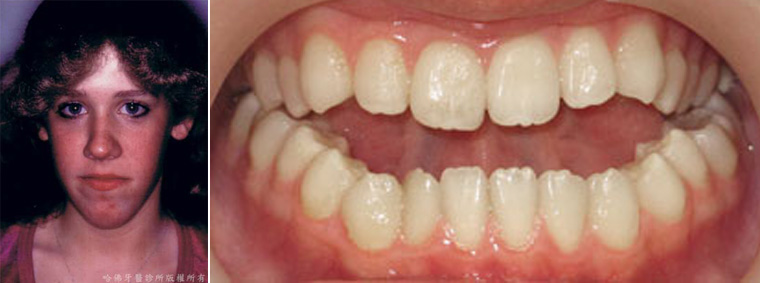

社會心理學研究顯示,由美觀觀點判斷,人體在外觀中,「臉部」為影響外觀上美觀的最重要結構(圖10);而在臉部外觀中,則「微笑」與「齒列」又為影響臉部外觀的最重要結構(圖11) 。

(圖11) 在臉部外觀中,則「微笑」與「齒列」又為影響臉部外觀的最重要結構。

當一個人存有「齒列不整」與「顎骨發育異常」時,會明顯造成口臉部外型的不平衡與美觀障礙。社會心理學研究資料顯示,外型不平衡的臉部與微笑可能會在「交友」、「求職」、「異性社交」 或 「競爭公職」上遭遇障礙(圖12)。

(圖12)當一個人存有「齒列不整」與「顎骨發育異常」時,會明顯造成口臉部外型的不平衡與美觀障礙。社會心理學研究資料顯示,外型不平衡的臉部與微笑可能會在「交友」、「求職」、「異性社交」 或 「競爭公職」上遭遇障礙。